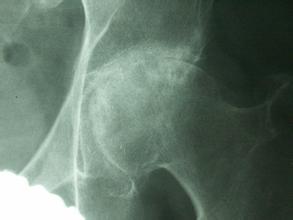

导读: 股骨头坏死了可以吃哪些蔬菜?股骨头坏死是较常见的一种骨关节疾病,治疗需要一定的时间。在治疗过程中,患者的合理饮食能起到很重要的作用,尤其是新鲜蔬菜,能补充人体营养,帮助身体康复。那么,股骨头坏死了可以

导读: 从哪些方面预防股骨头坏死?一种疾病的发病因素一般都是比较多的,能从许多方面来诱发疾病。因此要预防疾病,也要从多方面入手,比如股骨头坏死。这是一种较常见的骨病,影响大,要避免股骨头坏死危害自身健康安全,

导读: 股骨头坏死在天气变化时如何保护自己?生活中,很多人都会受到股骨头坏死的困扰。此病属于慢性隐性疾病,其病变过程复杂而漫长,而且容易受到天气变化的影响。天气对股骨头坏死的影响主要体现在寒冷和潮湿这两种天气

导读: 生活中如何调理股骨头坏死?股骨头坏死是一种很常见的疾病,患上股骨头坏死对我们简直就是一种噩梦,那么现实生活中我们又如何在家调理呢?又该怎样调理呢?下面由我院骨科专家为大家推荐一种有效的家中调理的按摩办

导读: 如果说大家平时的饮食不规律的话,那么我们可能患上很多的疾病的,既然饮食可以引起很多的疾病的发生,那么饮食自然也是可以有效控制疾病的病情的发展,而针对股骨头坏死也是这样的。在平时可以注意一下自己的饮食,